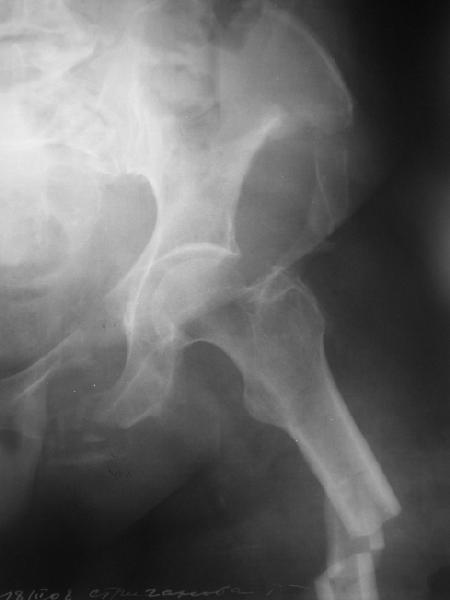

Здравствуйте уважаемые коллеги! Поступила пациентка, 61г, через 1 месяц после травмы, с двусторонним ротационно-нестабильным повреждением тазового кольца: перелом боковых масс крестца с обеих сторон, переломы лонной и седалищной костей слева, отрывные переломы передних остей левой подвздошной кости, сегментарный перелом левой подвздошной кости. Кроме того у пациентки имеется сегментарный перелом левого бедра. Перелом бедра не вызывает вопросов - планируем блокируемый остеосинтез стержнем, а вот при обсуждении тактики лечения переломов костей таза возник вопрос о необходимости синтеза остей подвздошной кости, учитывая сроки с момента травмы и наличие остеопороза могут возникнуть технические сложности. Если у кого-нибудь собственный опыт или ссылки на литературу об отдаленных результатах при не восстановлении сгибательного аппарата бедра?

Уважаемые коллеги, в продолжение обсуждения перелома костей таза с отрывами остей досылаю R-снимки (КТ и КТ с 3d реконструкцией)